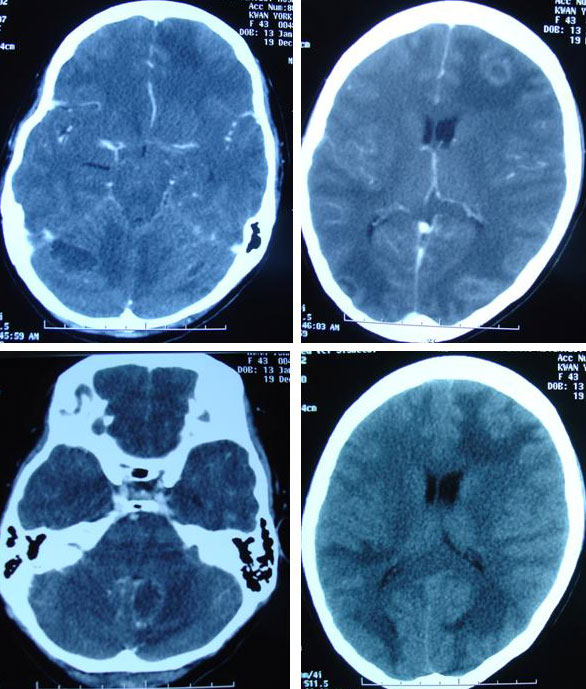

On 17 December 2008, York suffered headaches and was unable to sleep. A CT scan done on 19 December 2008, indicated multiple brain metastases.

Yee and her husband came to seek our help on 5 December 2008. Yee’s condition was serious. Her right arm was numb. She had no appetite. She was severely breathless. Even the supply of oxygen to her nostrils did not help at all. She told her husband she would rather die. In early February 2009, Yee was admitted to the hospital where the doctor suggested that she receive radiation to her brain. It was not to be – she died even before the treatment.